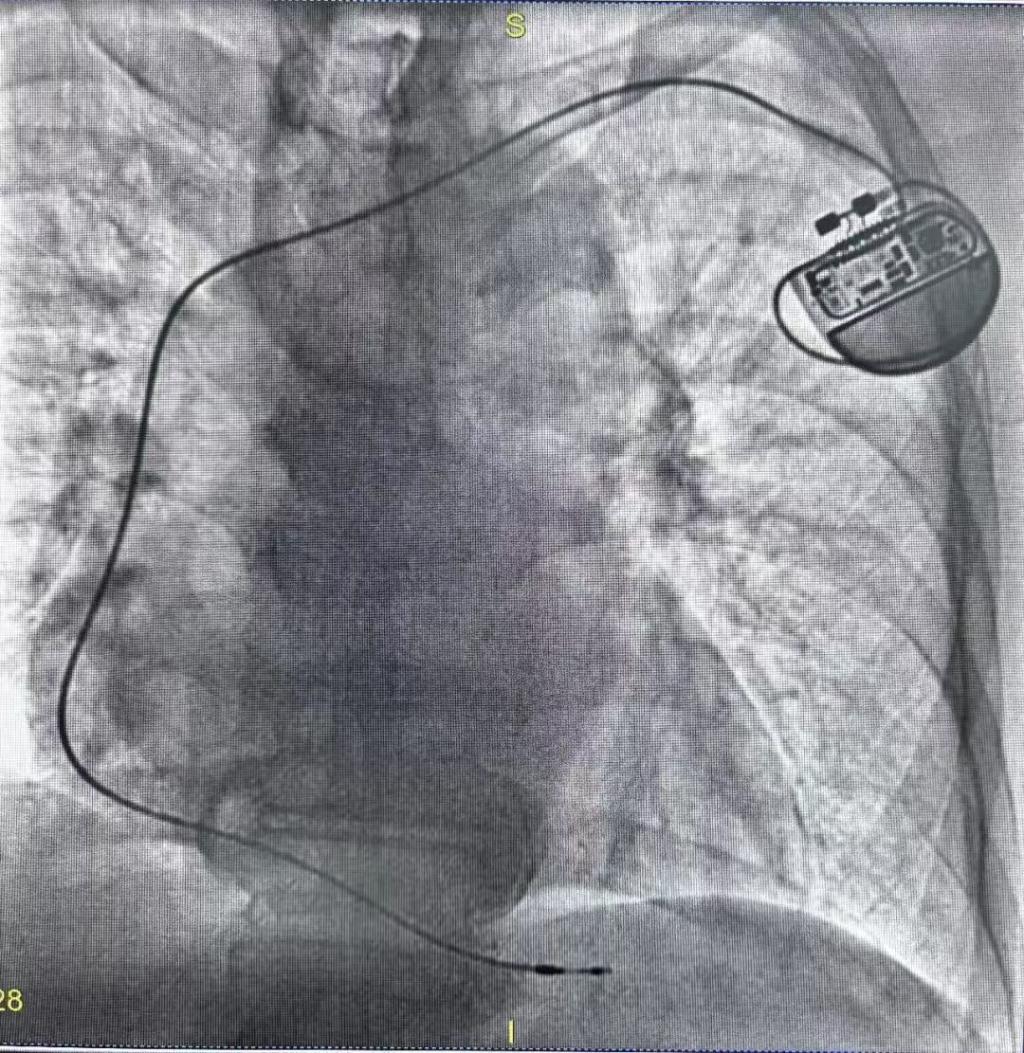

手术当日,我院心血管病介入团队在重庆医科大学附属永川医院心血管内科主任李志勇教授指导下,顺利为患者实施了单腔永久性起搏器植入术。考虑到患者高龄,有阵发性心房纤颤发作,采用传统右心室起搏可能会增加心衰和心房纤颤的反复发作,故决定采取左束支区域起搏,这样更符合生理性起搏,历时1个多小时,手术达到预期效果,起搏阈值、感知、阻抗等各项测试指标均符合标准要求,起搏器的起搏、感知、带动能力良好。

术后影像